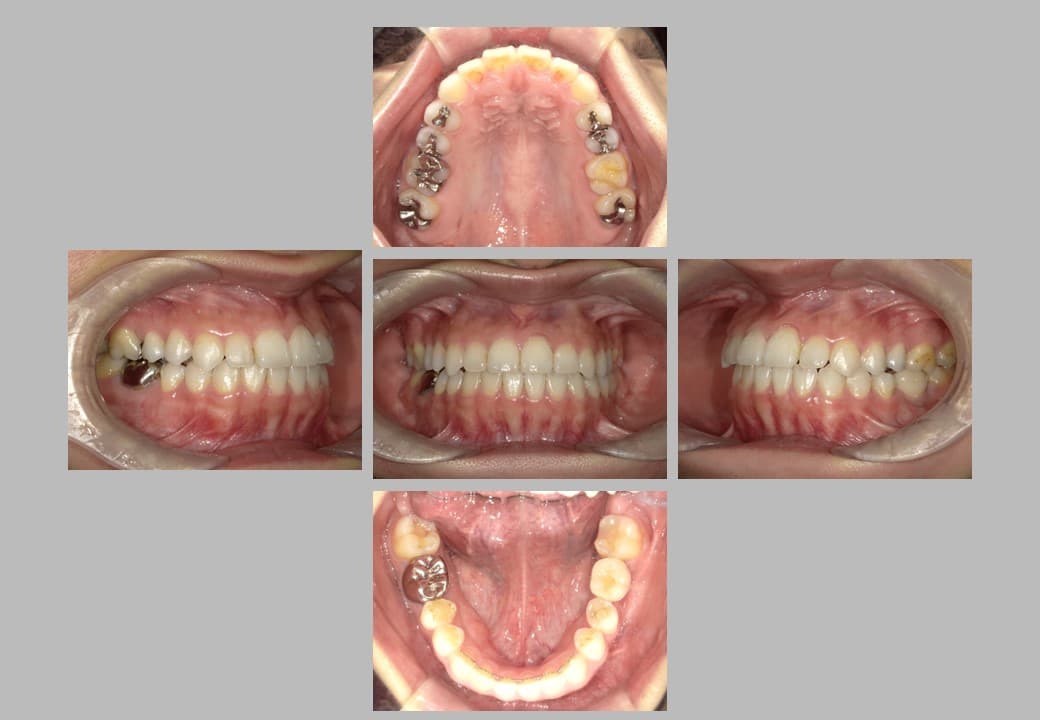

• 治療前